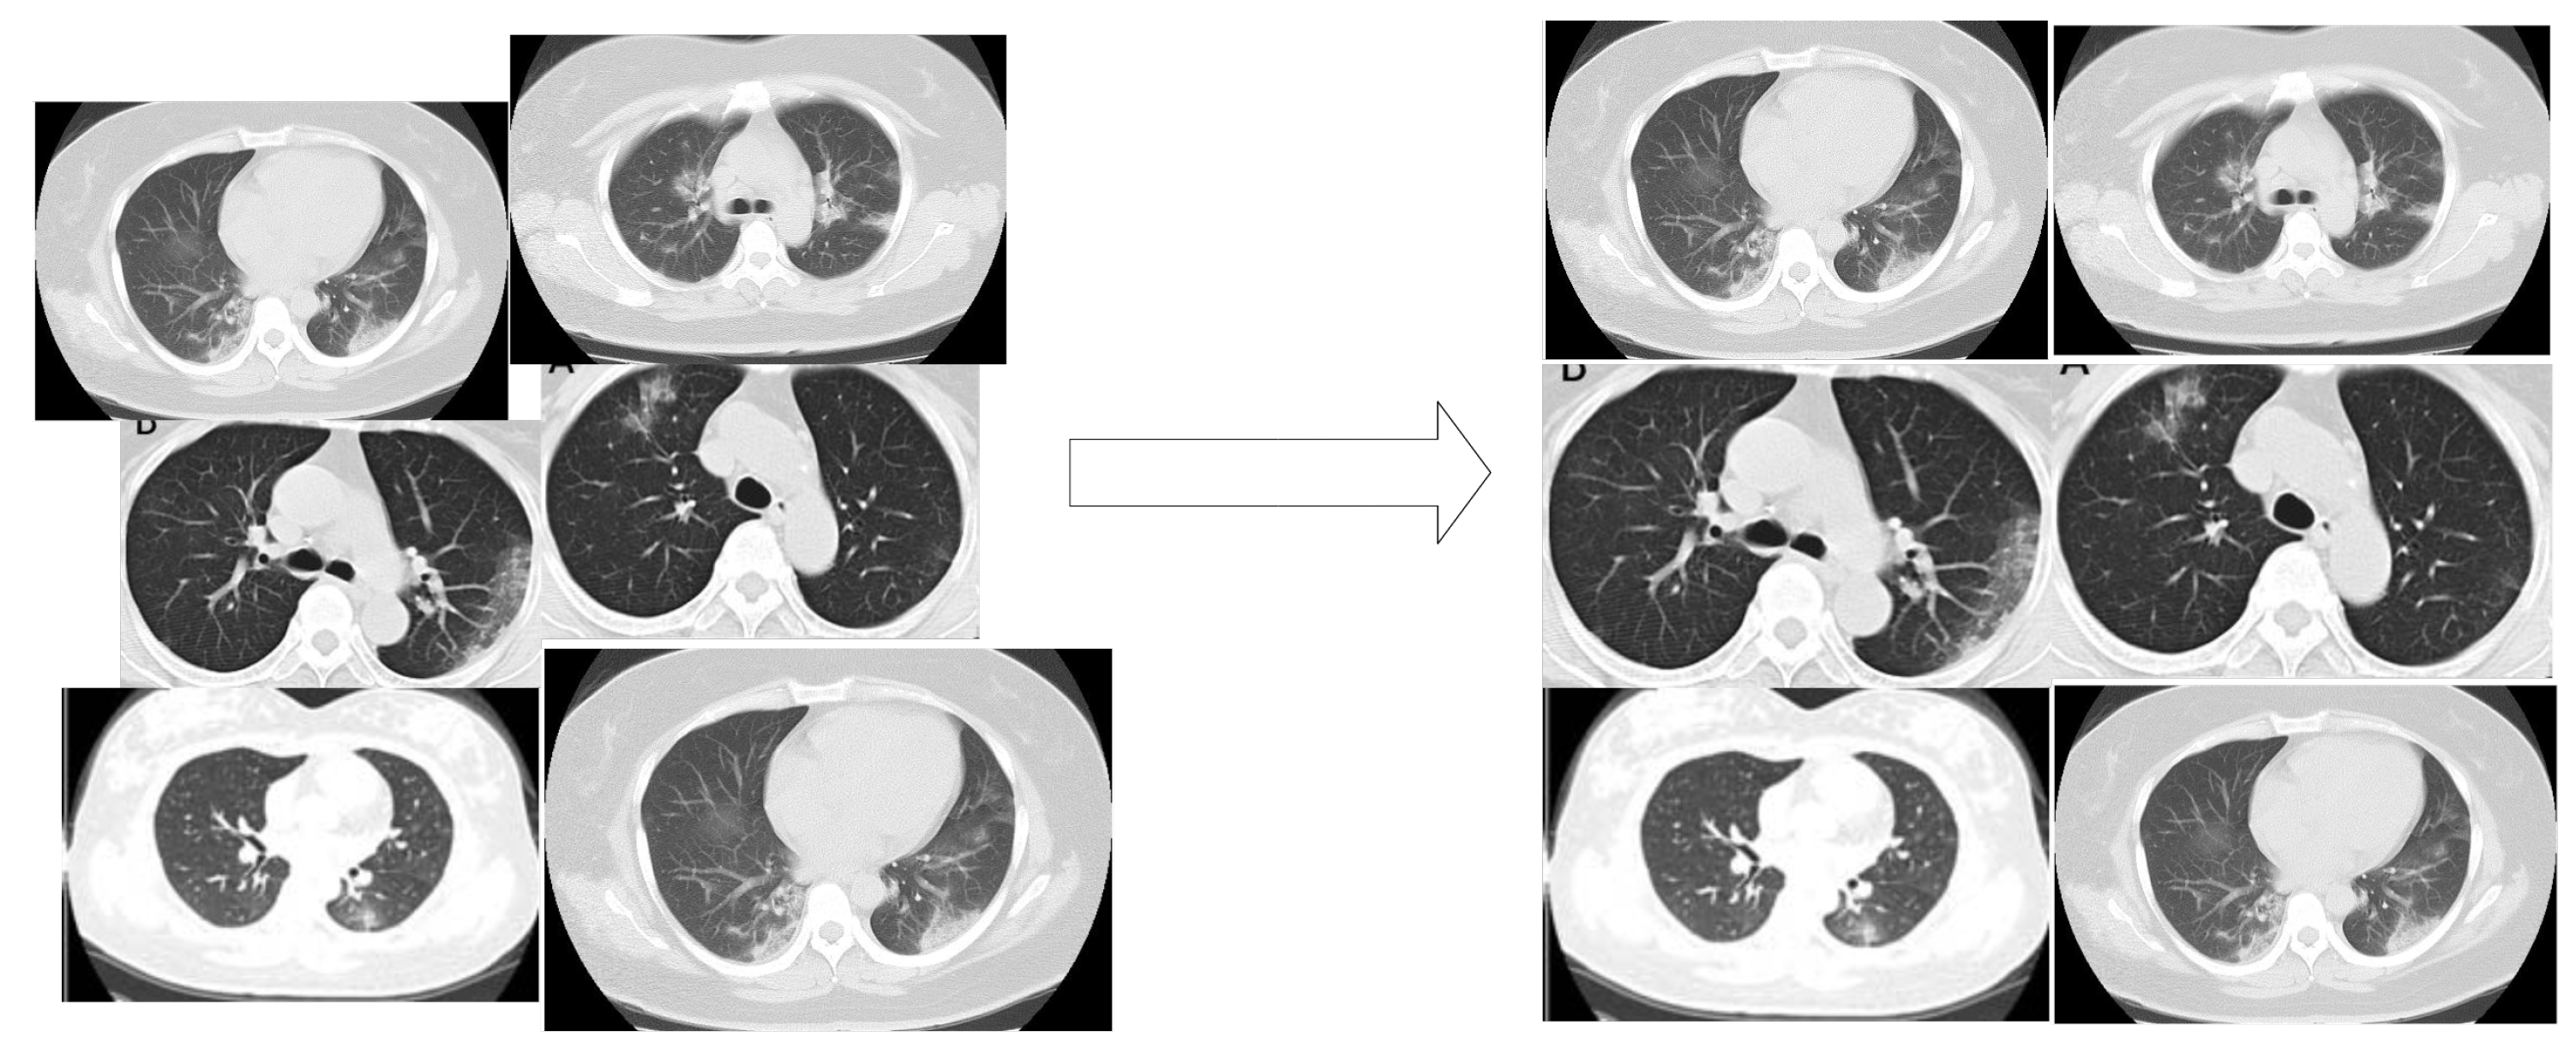

2.1. Problem Statement

2.3.2. Modified Enhanced Super Resolution GAN Plus (MESRGAN+)

Transition of Super Resolution by GAN

MESRGAN+ Architecture